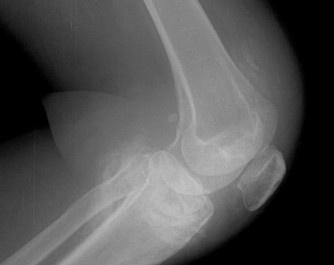

- 常見癥狀:膝關節(jié)水腫、疼痛、活動受限、跛行、膝關節(jié)屈伸活動受限、下蹲困難、并伴有疼痛、關節(jié)周圍局限性壓疼、浮髕試驗陽性

滑膜炎(英文名:synovitis),是一種多發(fā)性疾病,其發(fā)病部位主要在膝關節(jié)。膝關節(jié)是人體滑膜最多,關節(jié)面最大和結構最復雜的關節(jié),由于膝關節(jié)滑膜廣泛并位于肢體表較淺部位,故遭受損傷和感染的機會較多,膝關節(jié)滑膜炎主要是因膝關節(jié)扭傷和多種關節(jié)內(nèi)損傷,而造成的一組綜合癥。容易造成患者暫時或長期部分喪失勞動力,無論對患者和對社會的危害都較大。雖由許多有效的治療方法,但仍有許多患者仍不能治愈。尤其是部分中青年患者,要承擔許多社會和家庭責任,同時又在長期忍受疼痛的折磨。這無疑是急待醫(yī)務工作者解決的問題。